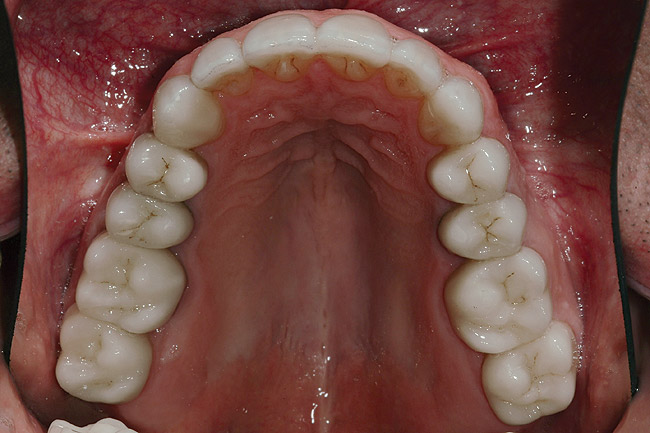

Figure 39: Maxillary postoperative view of the IPS e.max restorations.

Figure 39